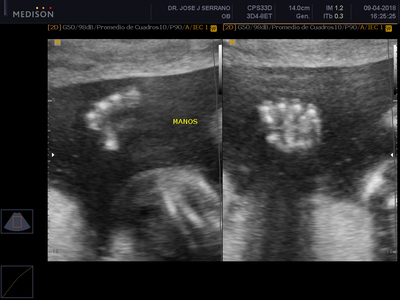

Esta ecografía busca detectar anomalías fetales explorando detalladamente cabeza, cara, tórax, abdomen, genitales y extremidades, así como todos los órganos del bebe (cerebro, corazón, pulmones, riñones, etc). También se tomarán las medidas fetales para compararlas con el tiempo de embarazo y descartar problemas de desarrollo y crecimiento. Además, se evaluarán los movimientos del feto, su patrón de respiración, tono fetal, flujo sanguíneo, entre otros.